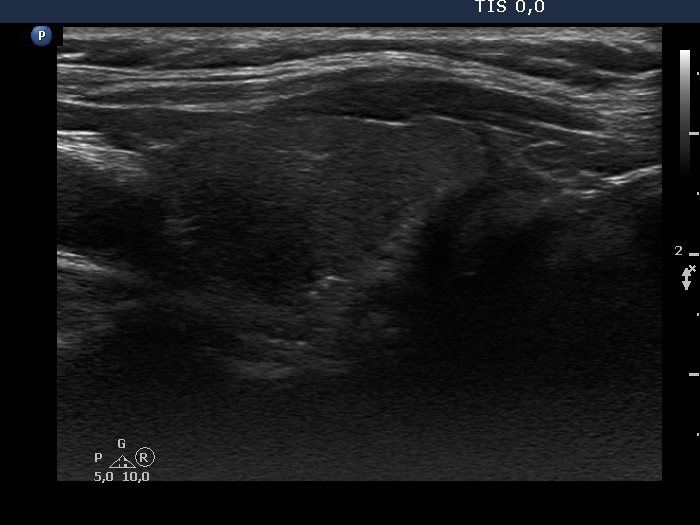

Right lobe, longitudinal scan

Left lobe, longitudinal scan. There is a more hypoechogenic area in the upper dorsal part of the lobe.